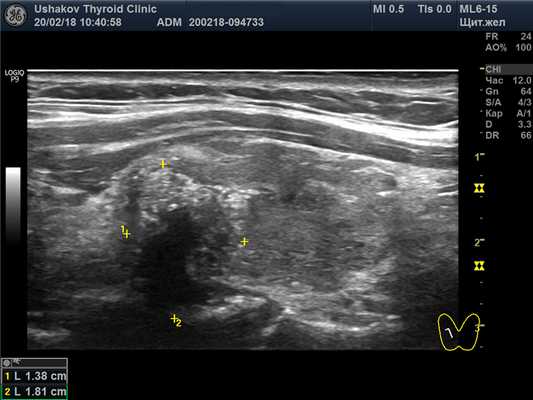

| Рисунок 4. Узел верхней (краниальной) части правой доли щитовидной железы (ограничен желтыми метками). Признаки рака узла: 1) неправильная форма, 2) неравномерный край узла, местами прерывистая граница, 3) значительно гипоэхогенная (темная) зона внутри узла, постепенно переходящая в остальную ткань, 4) микрокальцинаты. Класс по TI-RADS соответствует 4С. | Рисунок 5. Изменённый регионарный лимфатический узел. Отношение сторон меньше коэффициента 2 (округлый), внутри определяется значительное разрастание ткани (признак метастазирования). |